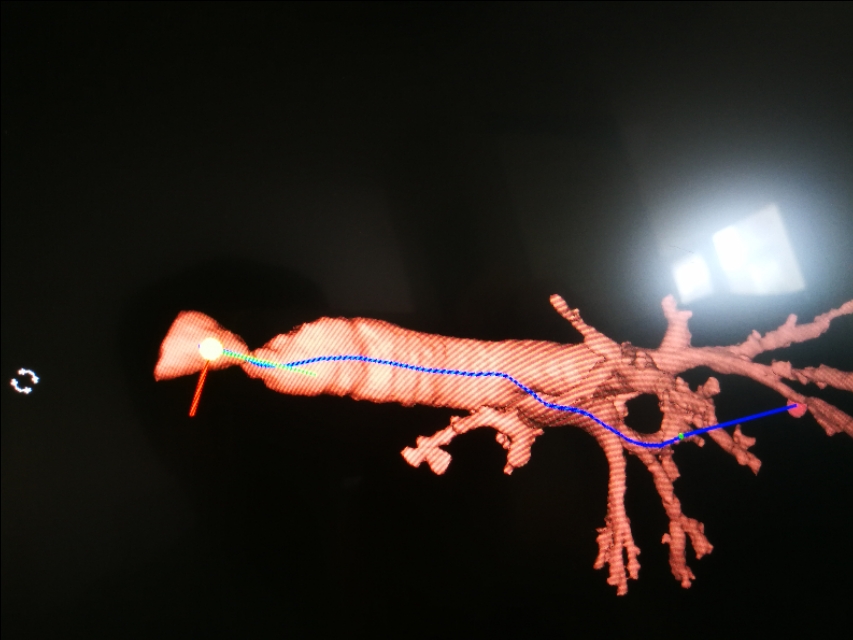

临床医生一看,他吸气有“三凹征”,这是大气道梗阻的表现啊。CT检查也证实了这一点。

我们想到了一年前他曾经插管上有创呼吸机,可能当时的切口,愈合后形成了瘢痕,瘢痕挛缩导致气道狭窄。

气管镜下可以更直观的看到气管到底多狭窄。只剩下几毫米的小孔了。

最简单的,先用电刀把周边放射状切开,再用球囊扩一扩,就能改善。

可是这里是“咽喉要道”,不,比咽喉要道更险峻!一旦做的过程中有出血,血块就可能堵在这,一下子可就要命了。甚至血丝稍微沾在狭窄的边缘,就可能喘息加重。到时候可能束手无策啊。打电话给耳鼻喉科,叫他们在手术室保驾,一旦不好,立即切开,耳鼻喉科医生说,我们做气管切开,估计需要20分钟!20分钟肯定来不及。哦,那就提前切开。在狭窄段以下切开,气体不从狭窄段走,我们就可以随便操作了!等狭窄解除了,再将切开处愈合。虽然对患者创伤大一些,但是可以做到万无一失。